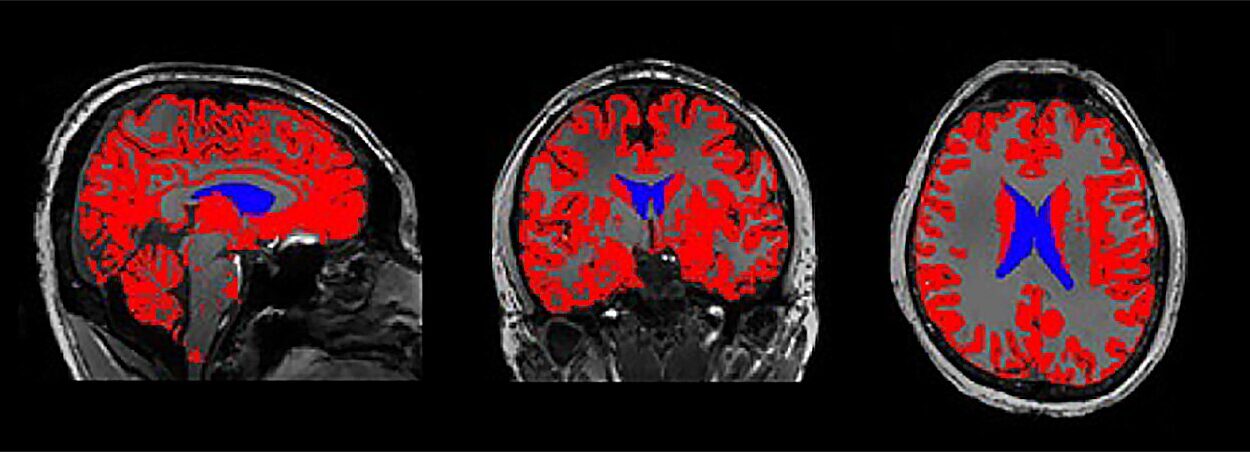

- Magnetic Resonance Imaging (MRI): The gold standard, offering detailed images of soft tissues. Specialized forms like functional MRI or diffusion tensor imaging reveal brain activity and connections.